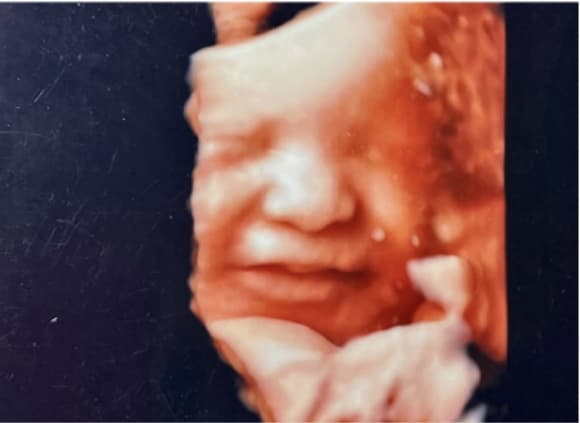

胎児エコー写真

4D胎児エコー写真

4Dエコー外来

• 妊婦健診の中でいつでもご希望の時に、お腹の中の赤ちゃんの状態を立体的に、そして動きまでリアルにご覧いただける超音波技術を用いた4Dエコー外来が受診できます。

• お腹の中のお子さまの様子を鮮明にご覧いただくことが可能です。(希望者のみ:2,160円/回)

※当日の胎児の向きや、姿勢によって必ずしも顔がはっきり見られるとは限らないため、費用は見えたときのみいただいております。

(30週)

(36週)

• 4Dエコーではここまで鮮明に赤ちゃんの様子が確認できます

4Dエコーではここまで鮮明に赤ちゃんの様子が確認できます

• 顔の輪郭もわかるほど、4Dエコーは鮮明です

顔の輪郭もわかるほど、4Dエコーは鮮明です